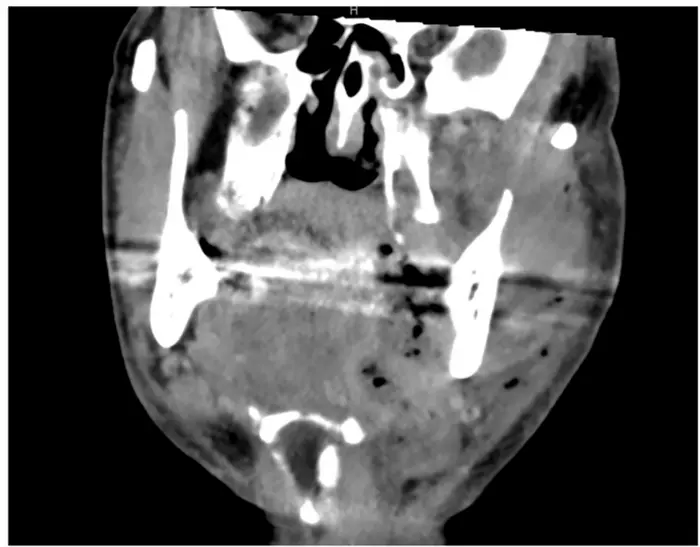

The authors highlight that contrast-enhanced CT scans are the most effective imaging tool for early diagnosis, as they help identify deep tissue damage and gas formation. Laboratory tools like the LRINEC score, often used to assess infection severity, are less reliable in head and neck cases and should not delay surgical action. The perspective reinforces that early and aggressive surgical removal of infected tissue, combined with broad-spectrum antibiotics and airway protection, is essential. Many patients require multiple surgeries and intensive care during the early stages of treatment.